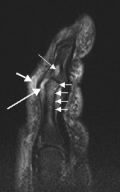

- T2-weighted MRI (sagittal) of index finger in PsA (mutilans form) showing probable erosion (increased signal) at base of the middle phalanx (long thin arrow), synovitis at the proximal interphalangeal joint (long thick arrow), soft tissue edema (short thick arrow), and diffuse bone edema (short thin arrows) of the proximal phalanx.